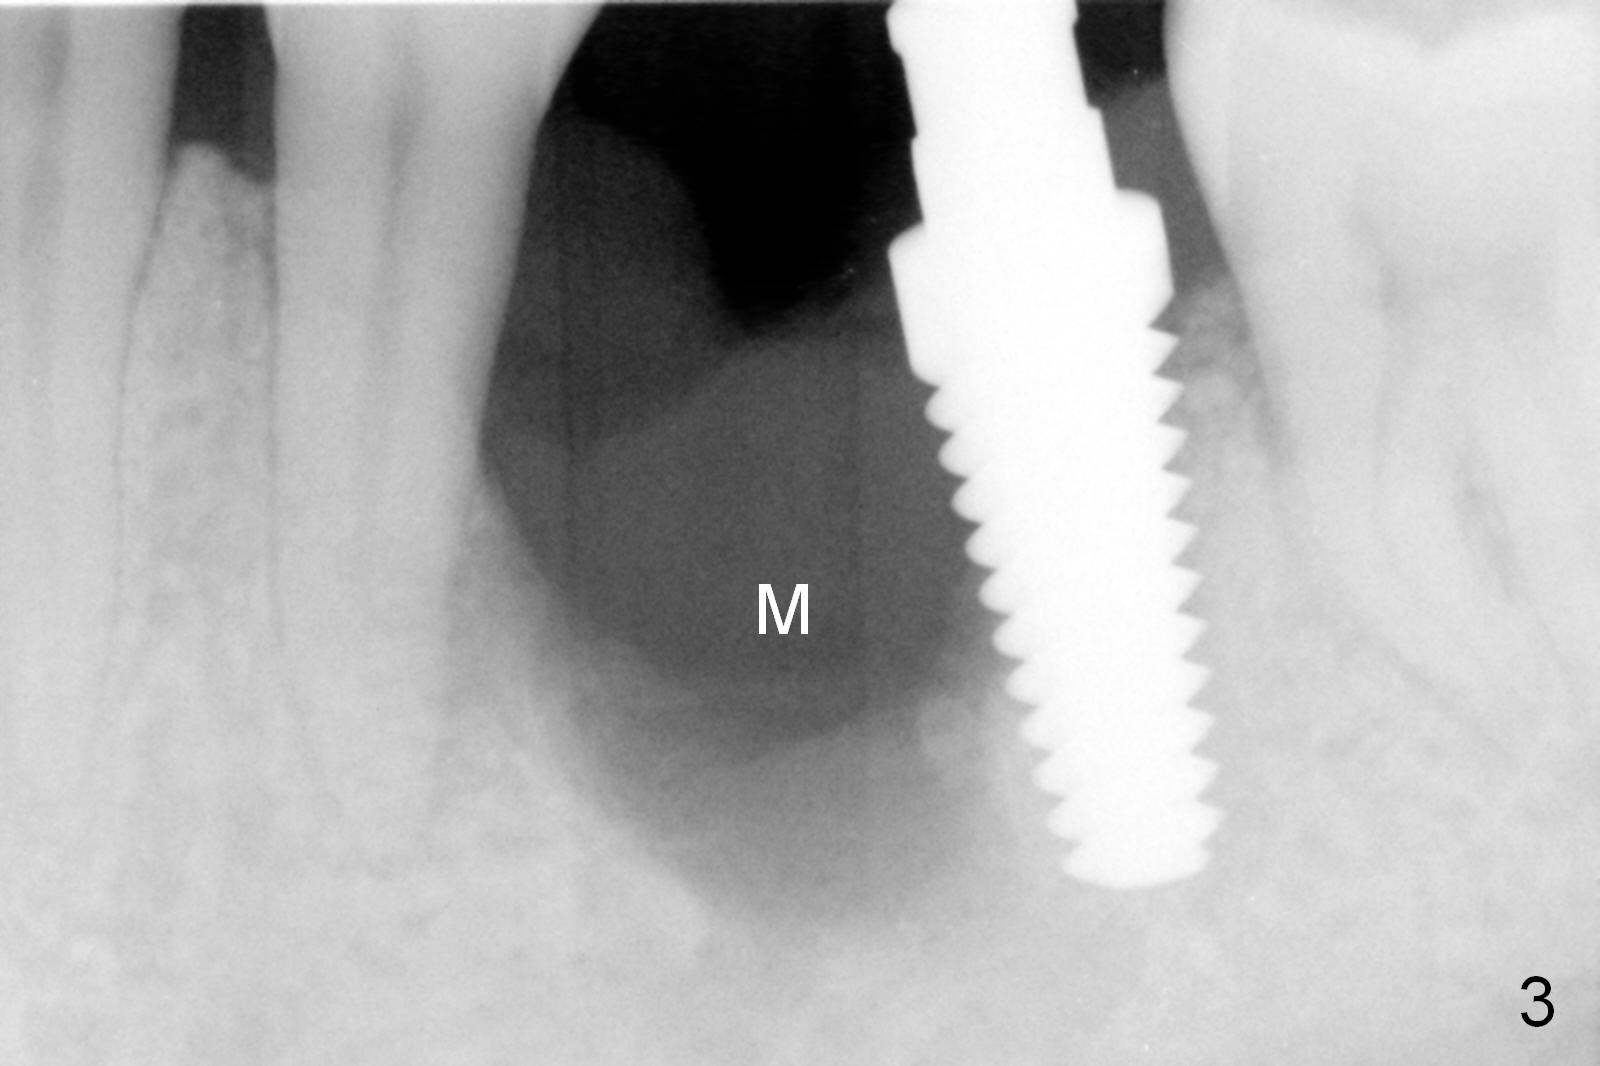

Considering the severe bone loss in the meisal socket, socket preservation is indicated if immediate implant is not feasible. Preop exam shows that the mesiobuccal gingival recession (Fig.1 MB) is not as severe as the mesiolingual one (Fig.2 ML). Because of oozing from the mesial socket, buccal envelop incision is made with flap raising to increase visibility. Probably due to periodontal infection, pain control is difficult. Osteotomy buccal to the Inferior Alveolar Canal proves to be risky. In addition, osteotomy in the mesial socket is more difficult than the distal one (Fig.3). Once the osteotomy depth is determined relative to the superior border of the Inferior Alveolar Canal (4 mm), the osteotomy depth increases by 2 mm. A 5.5x10 mm implant is placed with insertion torque ~ 35 Ncm (Fig.4); a 15 ° angled abutment (5.5 mm in diameter, 4 mm in cuff) is placed mesially. Then the abutment is turned lingually favorable for restoration (Fig.5), the remaining socket is filled with allograft/Osteogen (*) and Collagen Plug.